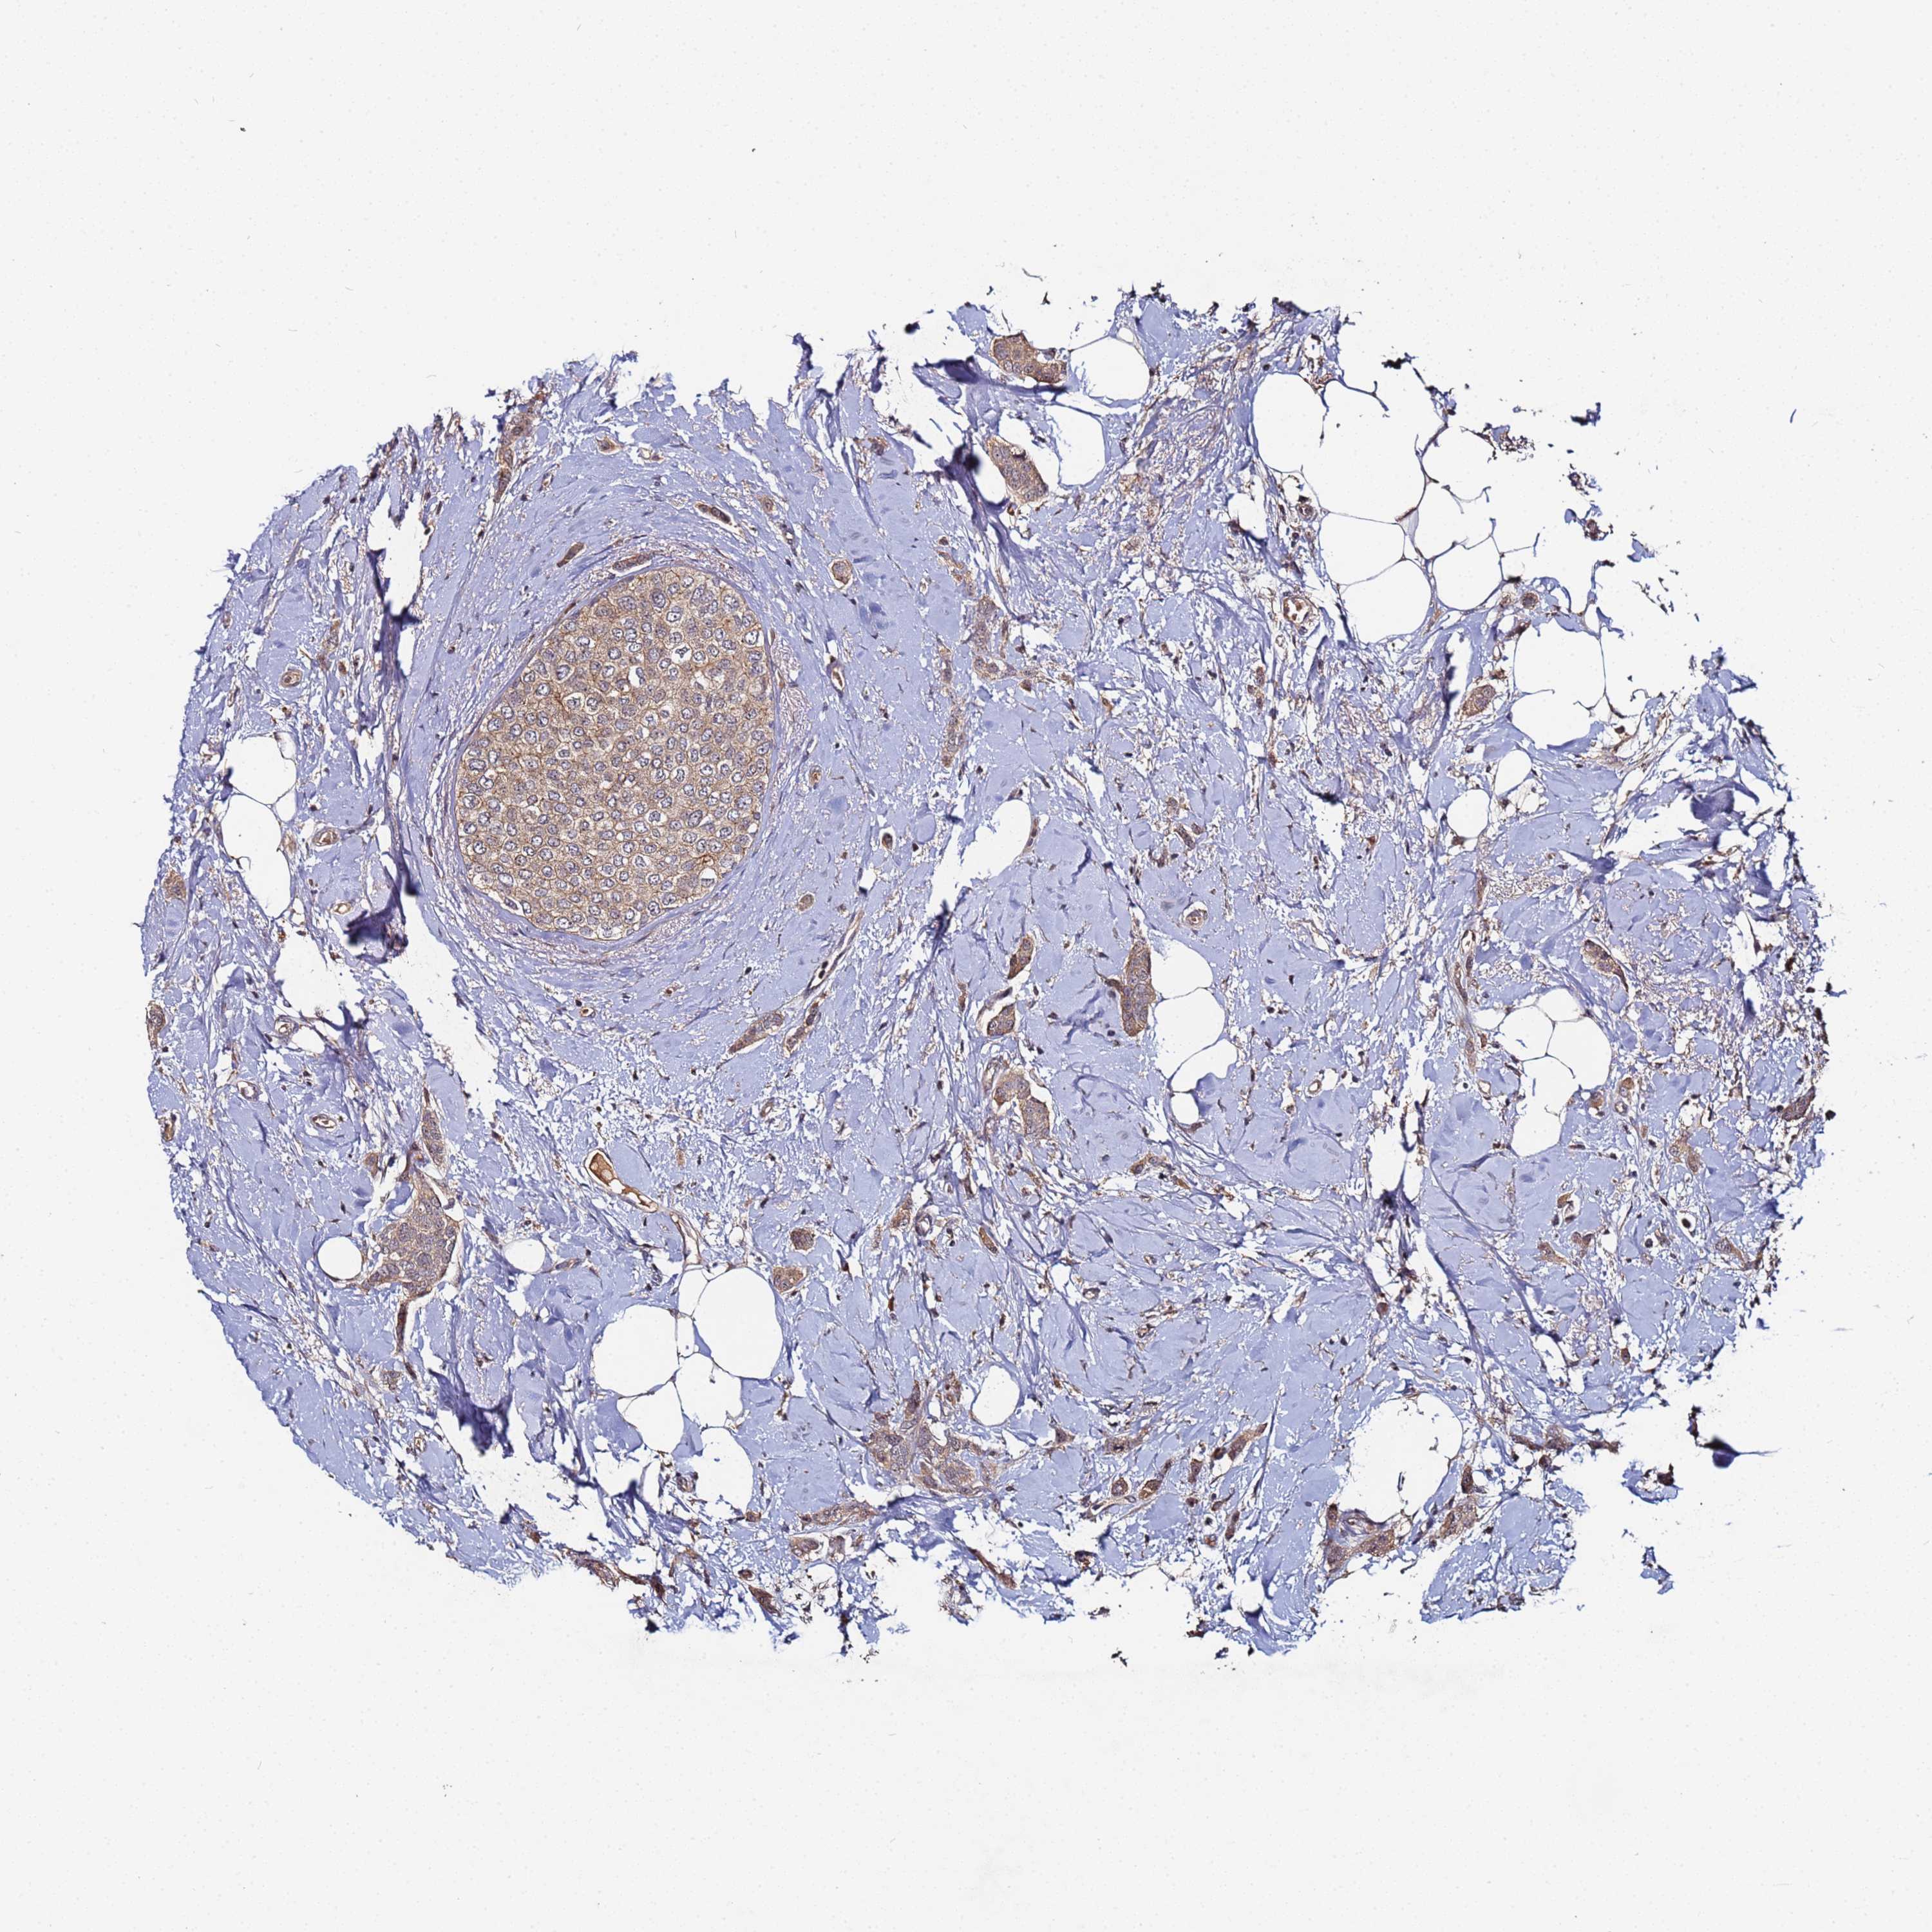

CANCER BREAST CANCER Show tissue menu

BRCA TCGA BRCA VALIDATION PROTEIN EXPRESSION